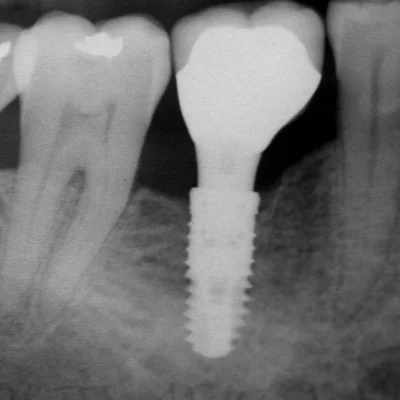

Implant Assessment

Evaluating bone density and jaw anatomy before dental implants.